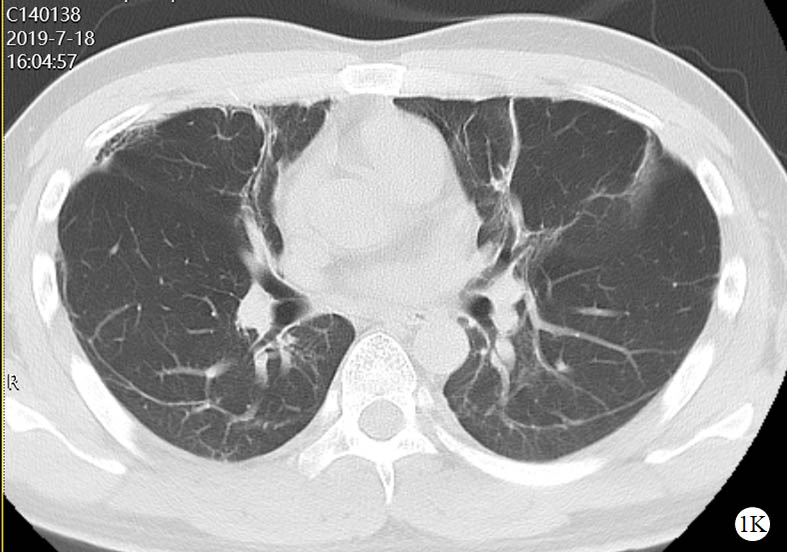

图 1 患者口服百草枯后胸部CT影像学变化

2019-07-18 CT图

2021-08-20 CT图